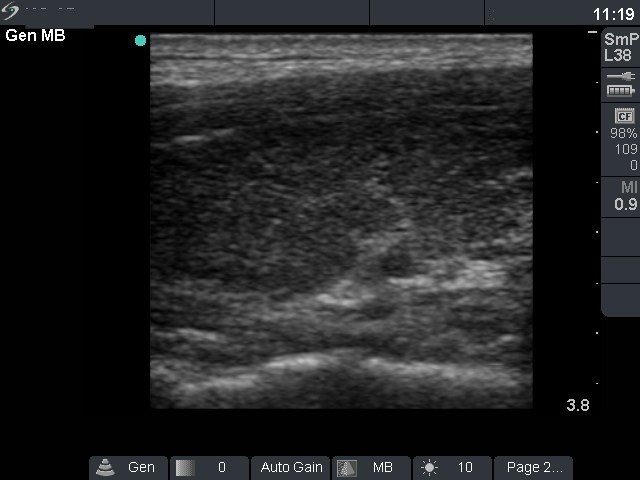

Four months after the first visit (ultrasonographic picture 5)

Left lobe, longitudinal view. The thyroid is hypoechogenic.